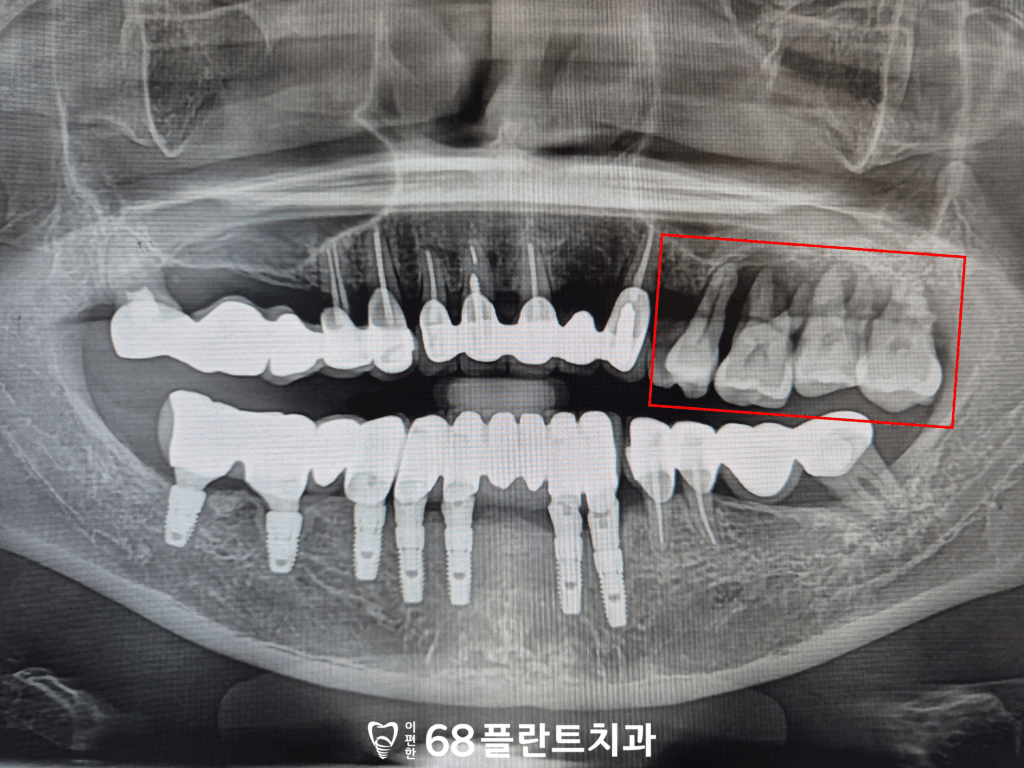

위 환자분께서는

왼쪽 위 치아들의 염증으로 인해

잇몸뼈가 녹아

철산역치과 이편한68플란트치과에

내원해주셨는데요.

파노라마 사진을 확인해보니,

이미 염증으로 인한 골소실이

상당히 진행되어 있었으며

남아 있는 뼈의 양이

충분하지 않은 상태였습니다.

이러한 이유로 치아도 많이

흔들리는 상황이라

염증이 더 진행되기 전에

발치를 해야 할 것으로 보였습니다.